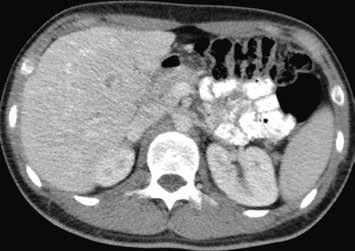

Nativně je v játrech ložisko, které je na CT hypodenzní (4), na MR izointenzní (5).

Na CEUS je v arteriální fázi patrný v levé polovině obrázku typický centrifugální charakter sycení ložiska, které je vidět v pravé polovině obrázku v B -módu (jako hypoechogenní) (6–8). Na CT (9) i MR (10) se ložisko (z obr. 4, 5) sytí homogenně, vyjma centrální vazivové jizvy, která zůstává hypodenzní.

V pozdní fázi je charakter ložiska stejný a nedochází k jeho vymývání ani na CT (13), ani na MR (14).

V centrální části ložiska je patrná vazivová jizva, která zůstává v arteriální fázi hypodenzní (9) a sytí se v pozdní fázi, kde je oproti zbytku ložiska hyperdenzní (13). Na MR je v T1-váženém obraze vazivová jizva hypointenzní (15), v T2-váženém obraze hyperintenzní (16).